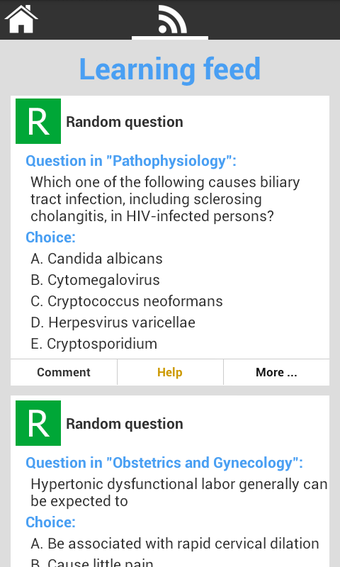

USMLE Exam Prep เป็นแอปพลิเคชัน Android ฟรีที่พัฒนาโดย quizworld ซึ่งเน้นการเตรียมความพร้อมอย่างละเอียดสำหรับการสอบ United States Medical Licensing Examination (USMLE) ให้แก่นักเรียน แอปพลิเคชันนี้ประกอบด้วยภาพพันธุกรรม ไฟล์เสียง และวิดีโอที่ครอบคลุมหลากหลายสาขา เช่น ชีวเคมีและพันธุกรรม รังสีหน้าอก วิธีการคลินิก อายุรศาสตร์ สูติศาสตร์และนรีวิทยา อายุรศาสตร์ประยุกต์ พยาธิวิทยา กุมารเวชศาสตร์ การวินิจฉัยทางกายภาพ ศัลยศาสตร์ จิตเวชศาสตร์ อาการสรีรวิทยา วิธีการคลินิก รังสีหน้าอก และการป้องกันโรค

นอกจากนี้ แอปพลิเคชันยังมีการ์ดฝึกหัดเพื่อช่วยให้นักเรียนปรับปรุงคำศัพท์และความรู้ในเชิงการแพทย์ แอปพลิเคชันนี้ใช้ง่ายและวัสดุการเรียนรู้จัดเรียงอย่างดี ทำให้นักเรียนสามารถนำไปใช้ได้อย่างง่ายดาย โดยรวมแล้ว แอปพลิเคชัน USMLE Exam Prep เป็นแหล่งข้อมูลที่ยอดเยี่ยมสำหรับนักเรียนที่กำลังเตรียมตัวสอบ USMLE และเป็นแนะนำอย่างมากสำหรับผู้ที่ต้องการเตรียมตัวสอบอย่างละเอียดและแบบปฏิสัมพันธ์